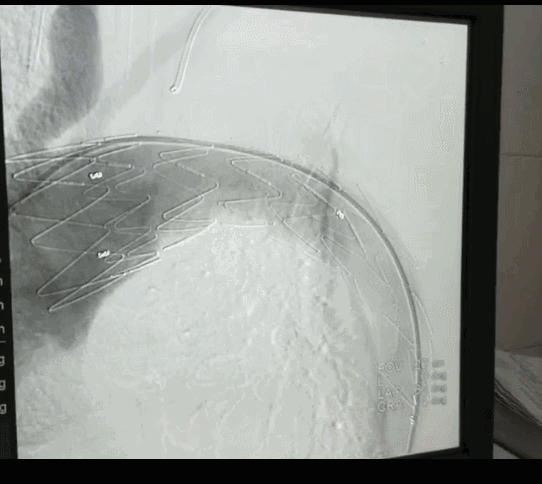

由于患者主动脉弓支架锚定区直径近36mm,需要大型号的支架,整个南阳市内没有,经联系只有郑州有,大雪封路,没有班车及快递,马上启动应急预案,连夜从郑州坐火车把支架运回,在住院第二天上午急诊手术,行腋腋动脉转流+主动脉覆膜支架植入+左锁骨下动脉弹簧圈封堵术,术后患者恢复顺利。

治疗原则:Stanford A型夹层已经发现均应积极手术治疗。Stanford B型夹层,药物治疗严格控制心率和血压,锚定区充足者,推荐TEVAR为治疗。